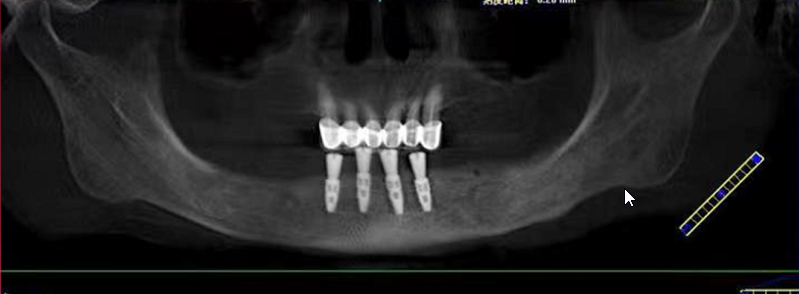

今天活动上有一位这样特殊的分享嘉宾——赖女士,今年69岁,需要种植的是下半口。赖女士为了想种好牙辗转了好几家医院,因为她的右边牙龈和舌头是连在一起的,去过其它医院说要割开才能种牙,后来打听到麦芽口腔姚院长临床经验丰富,过来看诊后,给出的主案可以用数字化导板进行种植牙,并不用割开原本连在一起的牙龈和舌头,赖女士听到此方案相当满意。

姚江武院长来为大家分享顾客术前牙片情况及种植方案。并现场讲解数字化全程导板种植技术与传统种植牙的区别和优势。

传统种植牙手术,被称为“自由手种植牙”,需要种植医生具备丰富的临床经验,从而准确判断种植牙植入牙槽骨的角度、深度。而数字化种植牙,通过制作数字化种植导板,导航辅助种牙,引导种植体精准植入,不仅创口小更舒服,而且避免盲种,吻合度更高,使种牙全程精准、微创,轻松享受缺牙重生的乐趣。